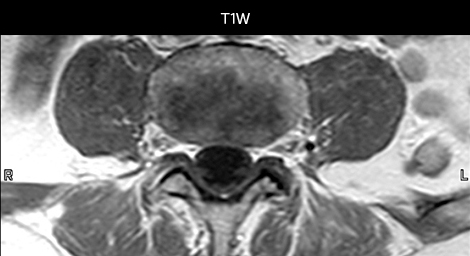

To minimize the time taken to perform scans, rapid MRI examination protocols (ExamCards) were developed, shortening the total scanning time to even less than 10 minutes in some exams. Techniques like mDIXON (modified DIXON) are used for robust capturing of fat-free MRI images in a hectic ED environment.

“We use mDIXON TSE extensively in our spine imaging in the emergency room,” says Dr. Karis. “It’s particularly nice in that it is very robust with regard to susceptibility type of problems that would come up with traditional spectral fat-saturated images; these problems are essentially eliminated with the mDIXON technique. In our ED environment it’s really nice to have the fat-free imaging that goes along with the mDIXON technique.